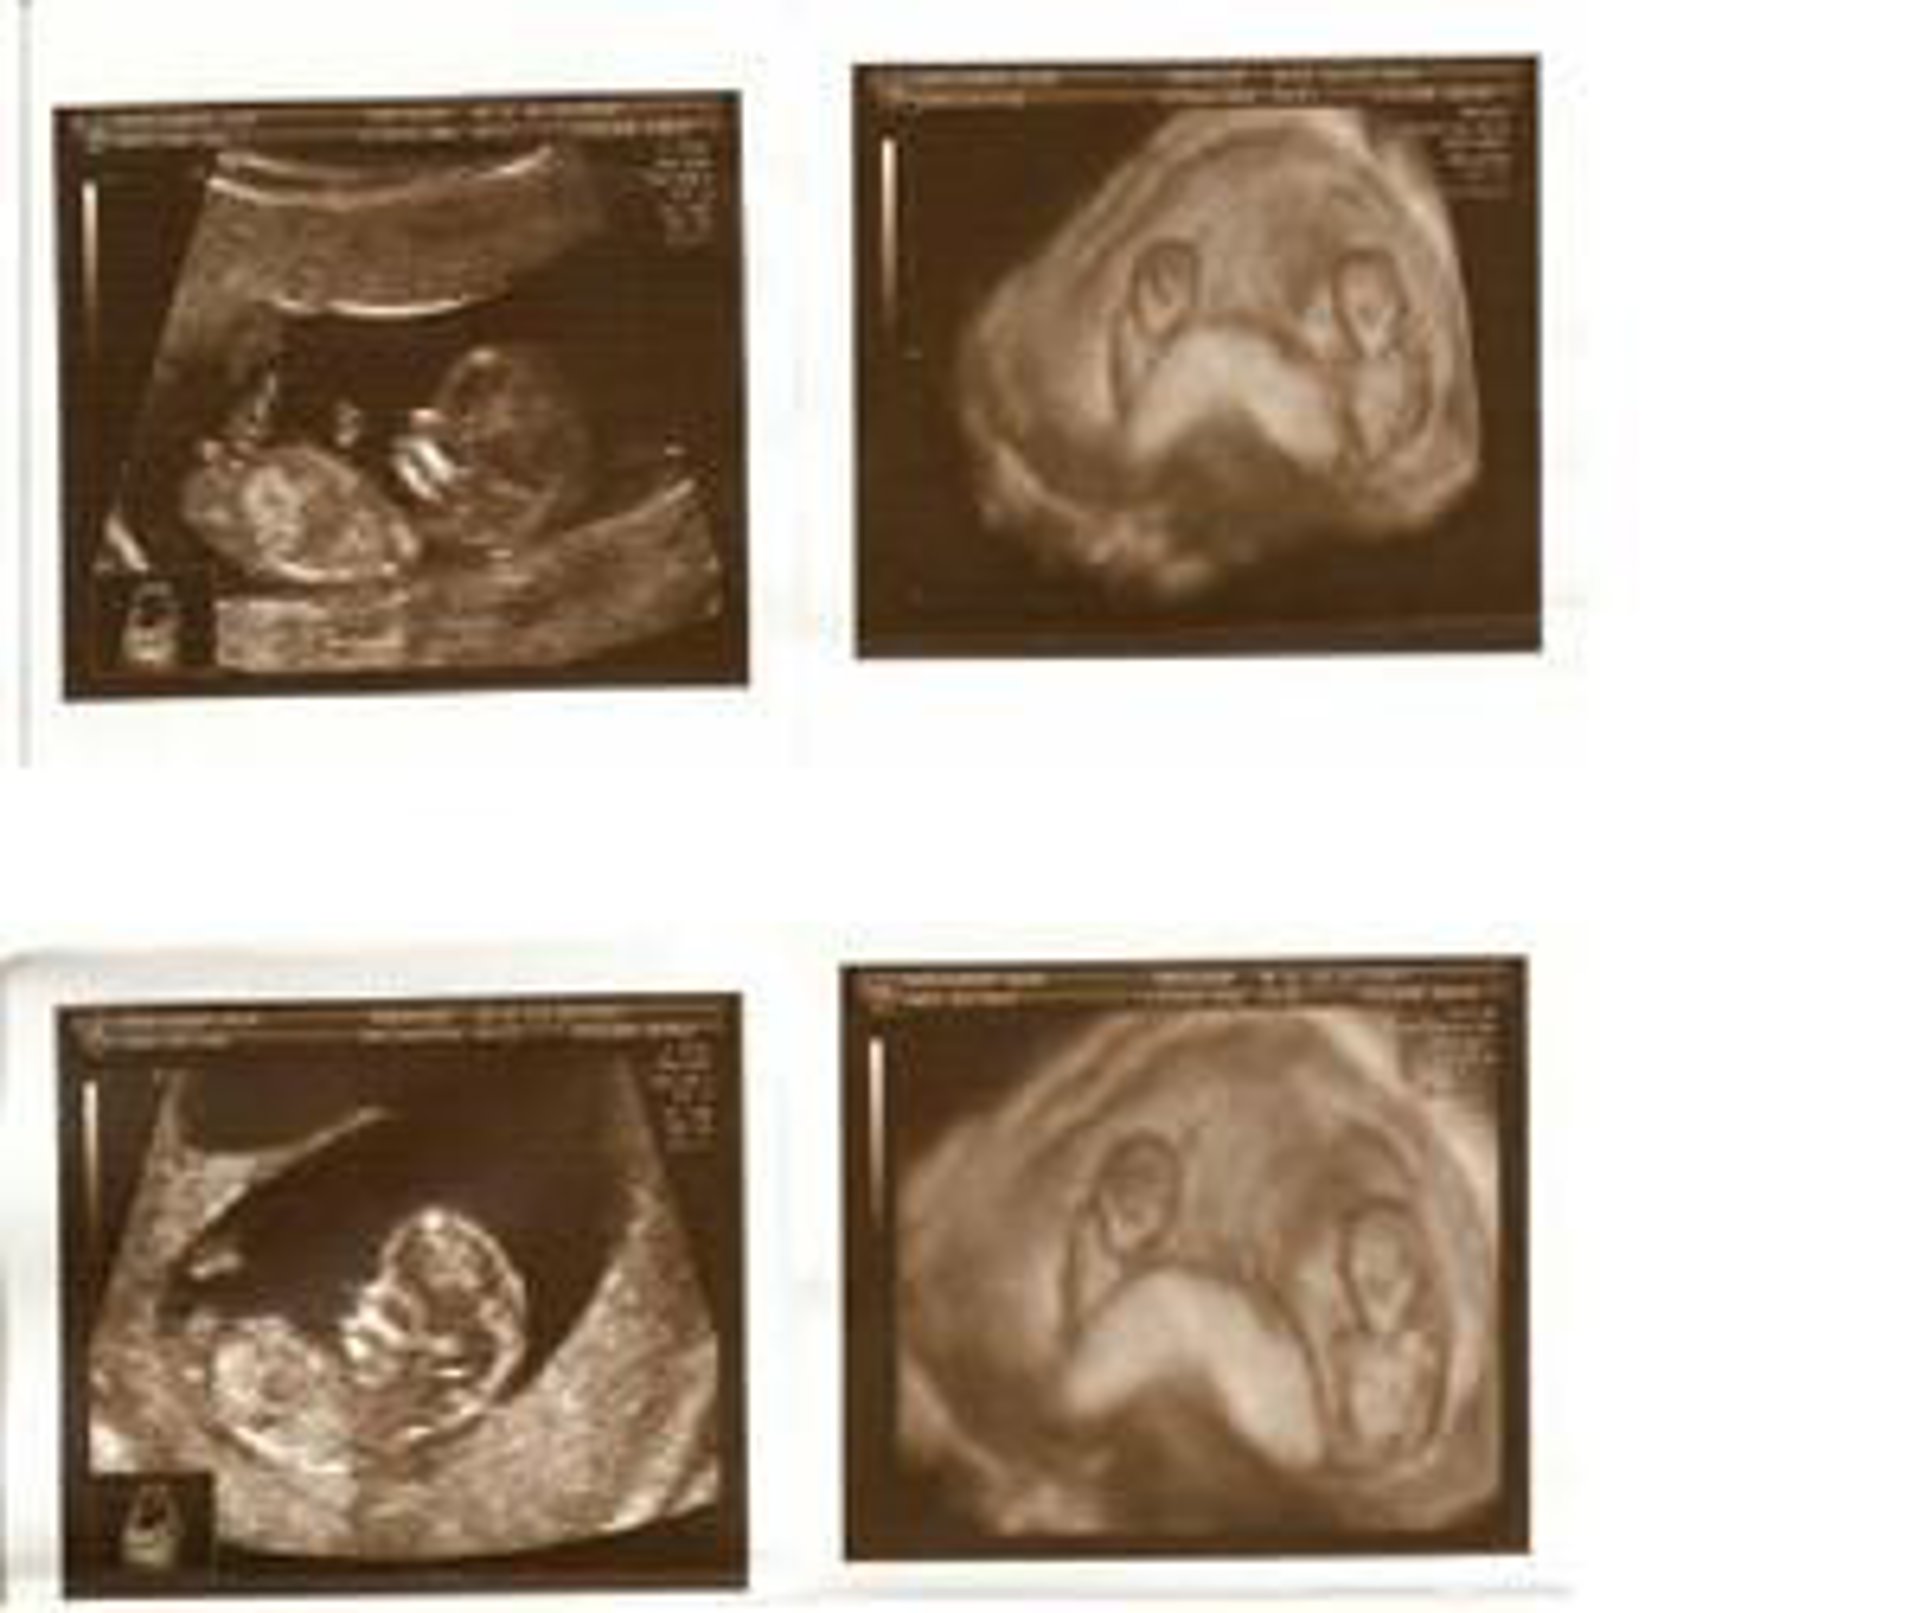

Al menos 259 mujeres han pedido preservar su tejido ovárico y ya se ha implantado a seis mujeres que, tras superar el cáncer, podrían decidir quedarse embarazadas en un futuro, según explicó hoy la responsable del programa de prevención de la fertilidad del Hospital Doctor Peset de Valencia, la ginecóloga María Sánchez, que ha seguido el caso de la primera mujer española que, tras superar un cáncer de mama, ha conseguido quedarse embarazada.